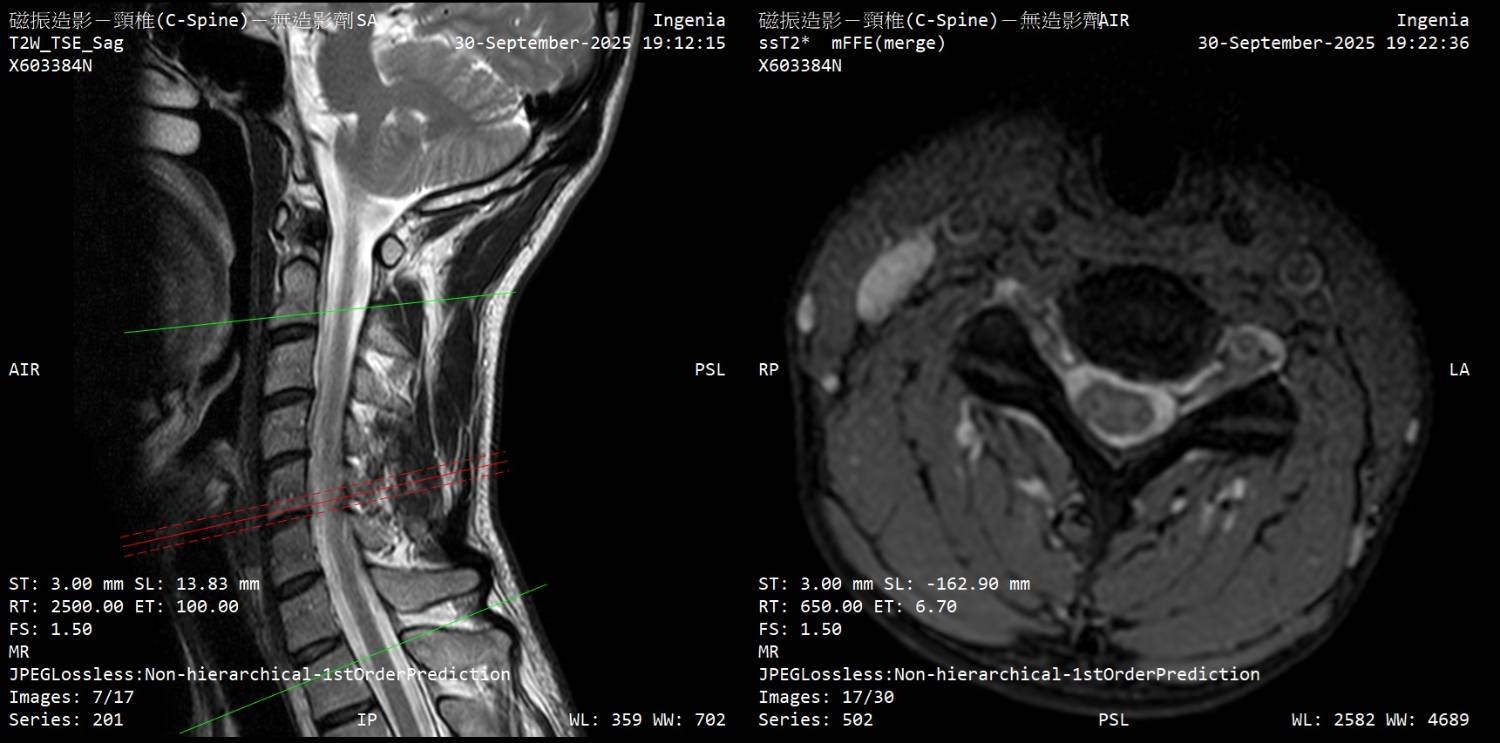

大家好 因为下列症状从2月开始断续发生,8月运动伸展上背後症状加剧 前往神经内科、神经外科就诊,目前不知道下步该往什麽方向? 该矫正姿势(脖前倾)? 复健科拉脖子? 寻求其他意见? 再观察? 症状 - 起床双手握不紧的感觉,白天正常 - 双手指尖感觉迟钝、左手臂外侧微麻感 - 双脚底有微微电流感(静止才感觉得到)、肌肉不定时抽动感、右小腿肚微麻 - 近半年有两次躺着以为有地震,结果没有震 检查 - 霍夫曼测试阳性、双膝反射增强 - 动作诱发电位正常、感觉诱发电位颈到手异常 11.3ms (标准<11ms) - 上肢神经传导正常 (一家正常/一家右正中神经异常) - 下肢神经传导左小腿/脚背异常 (以前受伤後遗症) 诊断 - 神内医师:颈椎有压迫、C5-C6黄韧带增生,建议先复健看看 - 神外医师:没有问题,应该是双手腕隧道症候群 颈椎MRI (全部) https://drive.google.com/drive/folders/1AmMB51gjrYYUIF8by9BEnTz1ahY3hbVp 文字报告 Unremarkable curvature of cervical spine No obvious herniated disc No obvious neuroforaman stenosis Suggest correlate clinical data. IMP: Unremarkable finding 神内医师判断可能压迫的部份 https://i.meee.com.tw/0E4JmY7.jpg

https://i.meee.com.tw/t3QgaWs.jpg

https://i.meee.com.tw/CsUmHf3.jpg

https://i.meee.com.tw/0C6bI5t.jpg